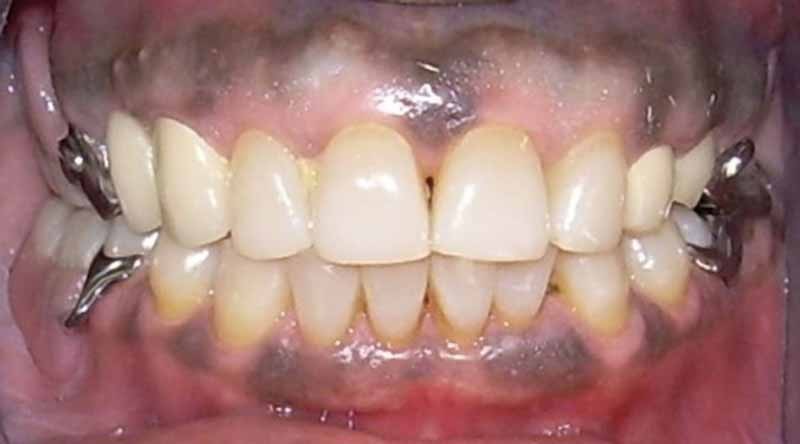

Les prothèses amovibles partielles métalliques sont-elles traumatisantes pour les dents supports ?

Comment suivre et évaluer le devenir des dents supports de prothèses amovibles partielles ? Y a-t-il une différence significative de reprises de caries entre les dents porteuses de crochets et les autres dents ?

Cependant, certains auteurs (2, 3, 4) relèvent à moyen terme, une survenue accrue de problèmes parodontaux, carieux ou de fractures sur les dents supports de crochets. Le contrôle permanent et la prévention sont donc nécessaires. Pour cette raison, un suivi et une évaluation des dents supports de prothèses amovibles partielles métalliques (PAPM) deux ans après leur pose ont été réalisés dans le service de prothèse du département d’odontologie de Dakar.